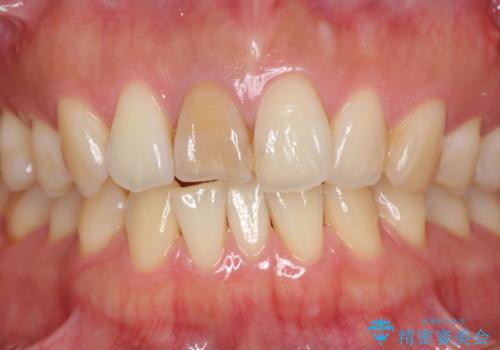

前歯の変色 根管治療と高品質セラミック歯科治療

- 前歯の変色の改善を求めて来院されました。

- 32万円(仮歯・ファイバーコア・ジルコニアクラウン×2)費用は治療当時の料金となります